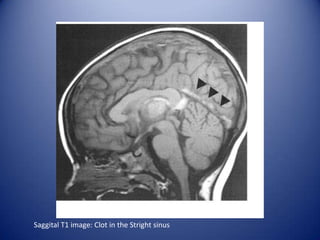

MRI in NP SLE

Multiple white matter lesions.

Cerebral infarction.

Cerebral hemorrhage.

Venous sinus thrombosis.

Atrophic changes.

Spinal cord disease.

Saggital T1 image: Clot in the Stright sinus